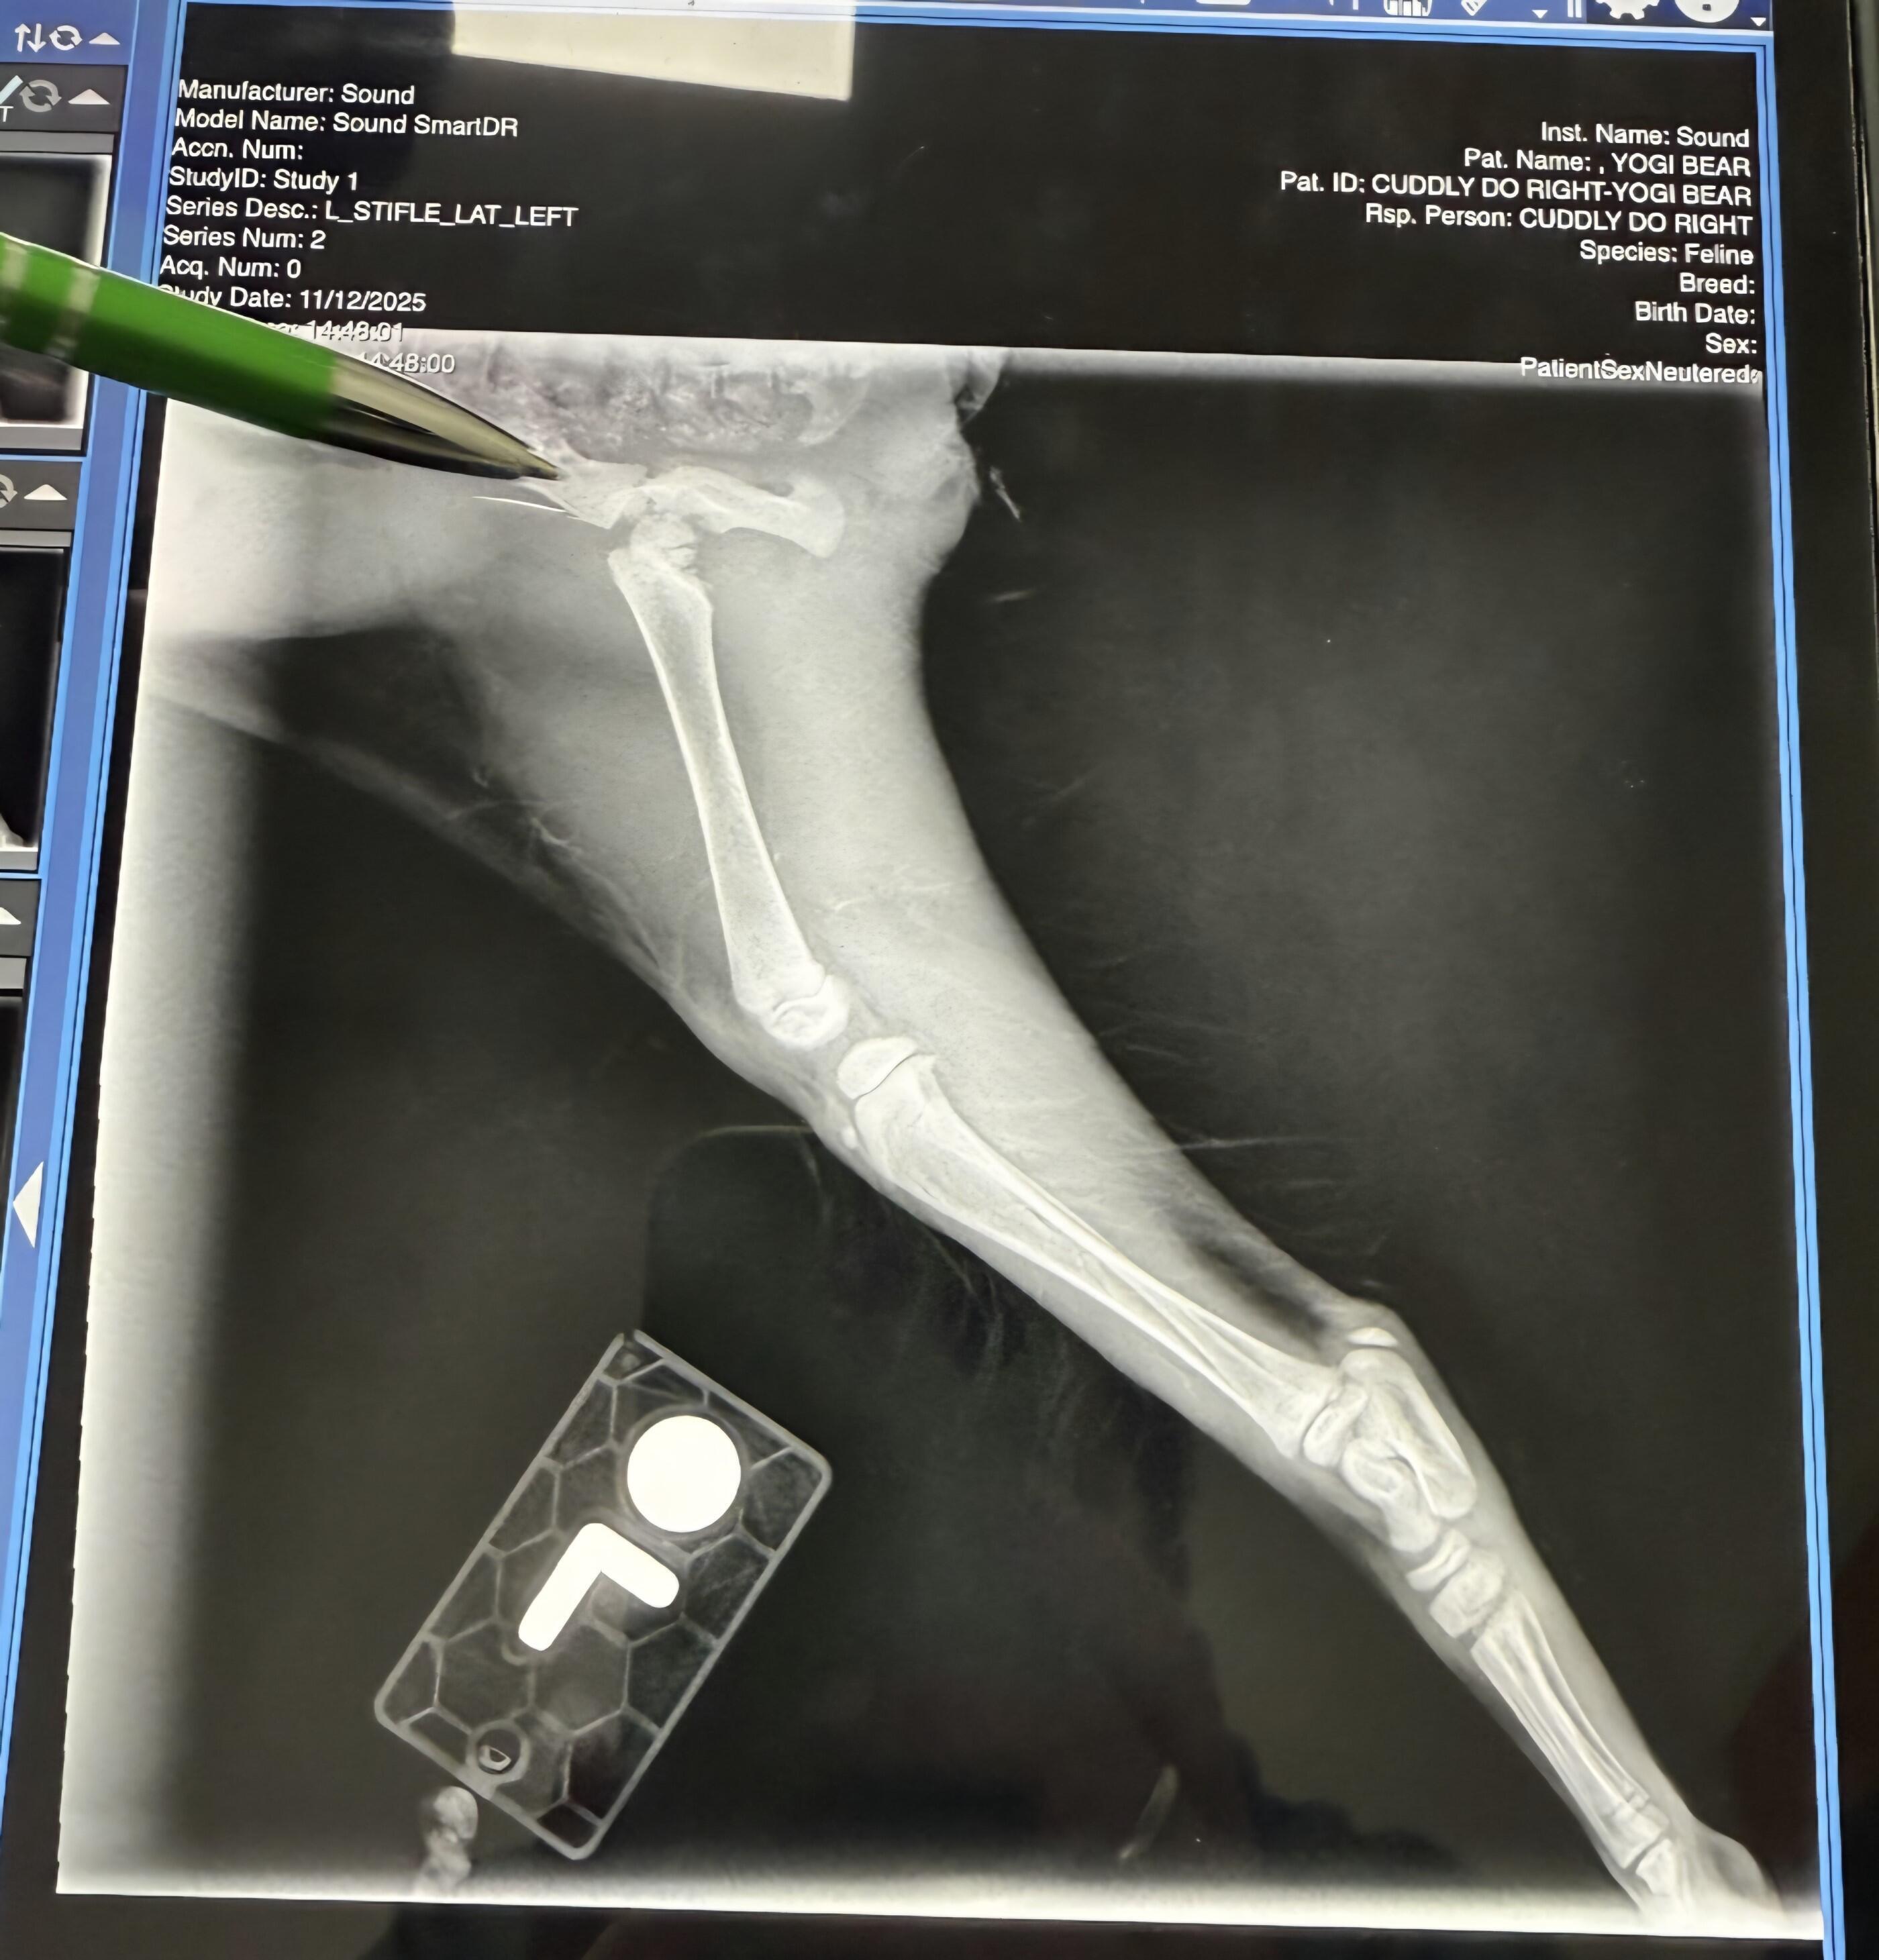

Yogi Bear has a real Boo Boo. Not a sidekick - a fractured femur!

Our Yogi is even cuter than her cartoon namesake but her "Boo Boo" is not at all a small, fun sidekick.

Yogi was found outside on the wintery-cold night of November 11th, hiding in the rim of a car's tire. Less than 24 hours later, her entire life has turned for the better! Except for one thing: she has a fractured and dislocated left femur.